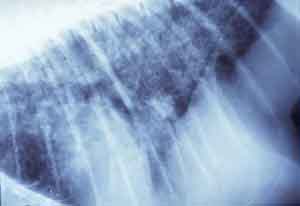

- Case 23-3. The A/P thoracic radiograph shows marked

right sided deviation of the cardiac silouette. The lateral thoracic

radiograph shows diffuse fluid density in dorsal lung fields.

-

- Thoracic radiographs demonstrated an increased pulmonary

interstitial pattern with air bronchograms bilaterally. The cardiac

silhouette was shifted to the right. Abdominal radiographs demonstrated

hepatomegaly and the presence of excessive gas in the stomach,

small intestine, and colon. Supportive treatment, including oral,

subcutaneous, and intravenous fluids, antibiotics, and vitamins

were administered, but response to treatment was minimal and

the monkey was euthanized in late 1998.